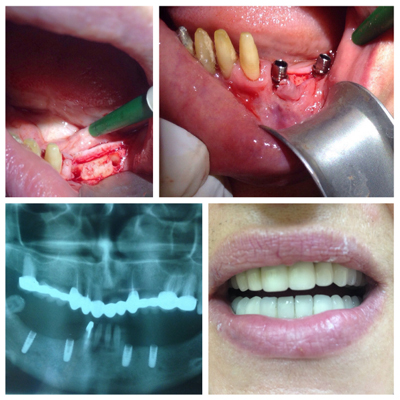

Dental implants are small, highly developed screws made out of pure surgical titanium. The implats are being placed (often by screwing) into the jawbone in order to replace missing teeth. A temporary crown (usually plastic) covers the gap until the implant healed into the bone.

After the healing period that can take between 3 months for the lower jaw up to 6 months for the upper jaw in wich the implant is firmly attaching to the jawbone, the permanently crown now can be attached to the implant.

Implants can be used to replace one or more missing teeth in the front as well for rear teeth. Also they can be used to support bridges or removable dentures in case of more missing teeth.